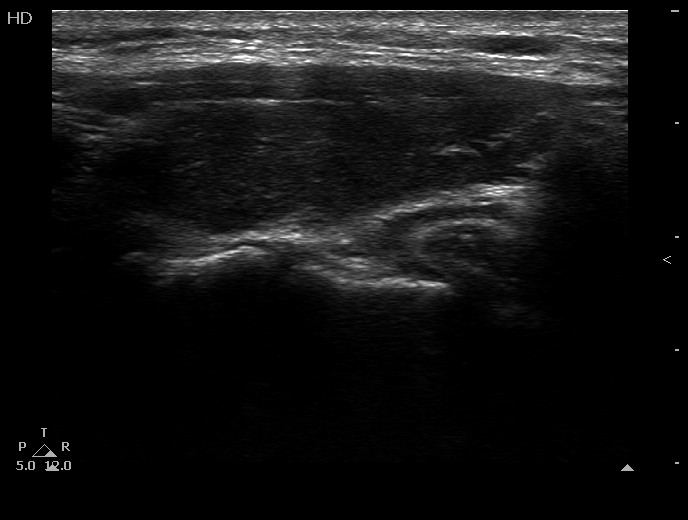

100 consecutive cases of papillary cancer - case 054 (ultrasonographic picture 8)

Left lobe, longitudinal view.